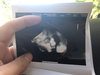

Ja już po wizycie :)

Szyjka nadal długa, rozwarcia brak.

Mała wazy już 2,8 kg także przez 2 tyg przybrała 400 g. Leży nadal główka w dół. Pokazała buźkę na usg, z takiej dziwnej strony i śmiesznie wyglada, ale zawsze coś :)